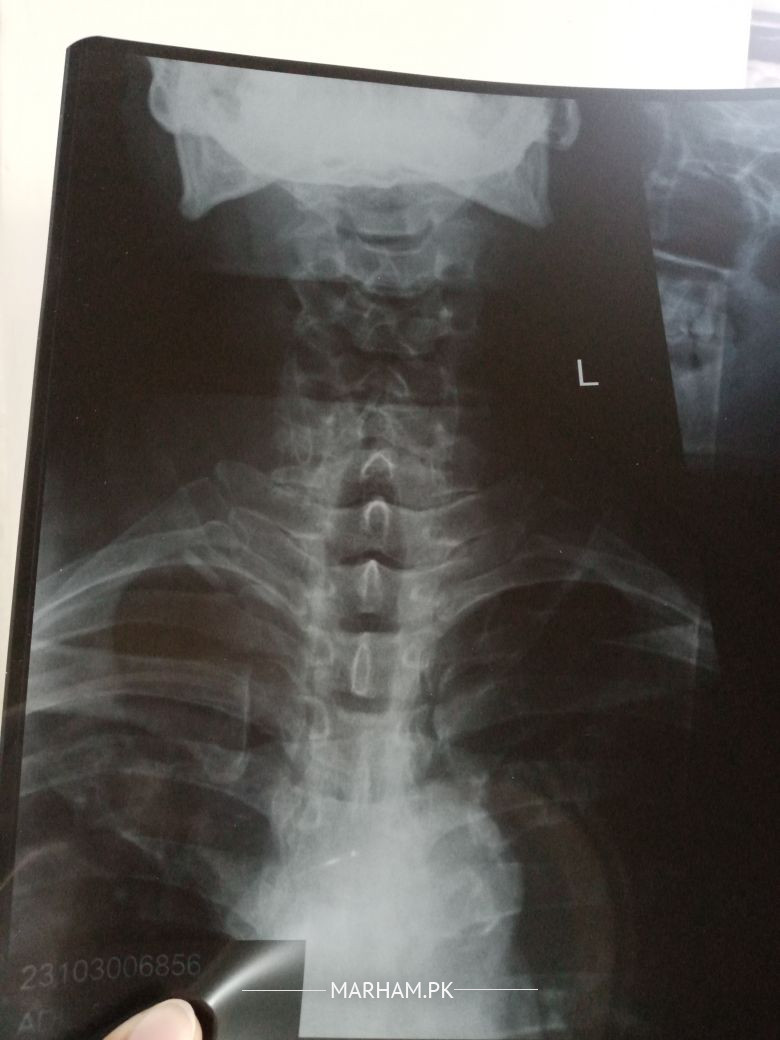

Talk to Radiologist on Neck Xray

Asking for Father Male 58 , Islamabad

Can someone please study these xrays. And point out the problem if any. Kindly tell the specialist needed for this

Patient has stiffness and pain in neck

little bit of straightening of spine and reduced space between C3 and C4